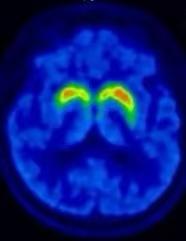

为攻克这一难题,陈玲教授团队创新性地采用了新型示踪剂进行突触前多巴胺能脑PET显像。这种示踪剂能够精准捕捉多巴胺神经元的早期微小变化,从而在患者尚未出现典型运动症状时,就发现潜在的脑功能异常。同时,借助人工智能技术对影像数据进行深度挖掘,研究人员能够从海量数据中识别出具有预测发病价值的异常模式。这种结合新型示踪剂和人工智能的方法,不仅提高了早期诊断的准确性,还为建立帕金森病前驱期预警模型奠定了基础。